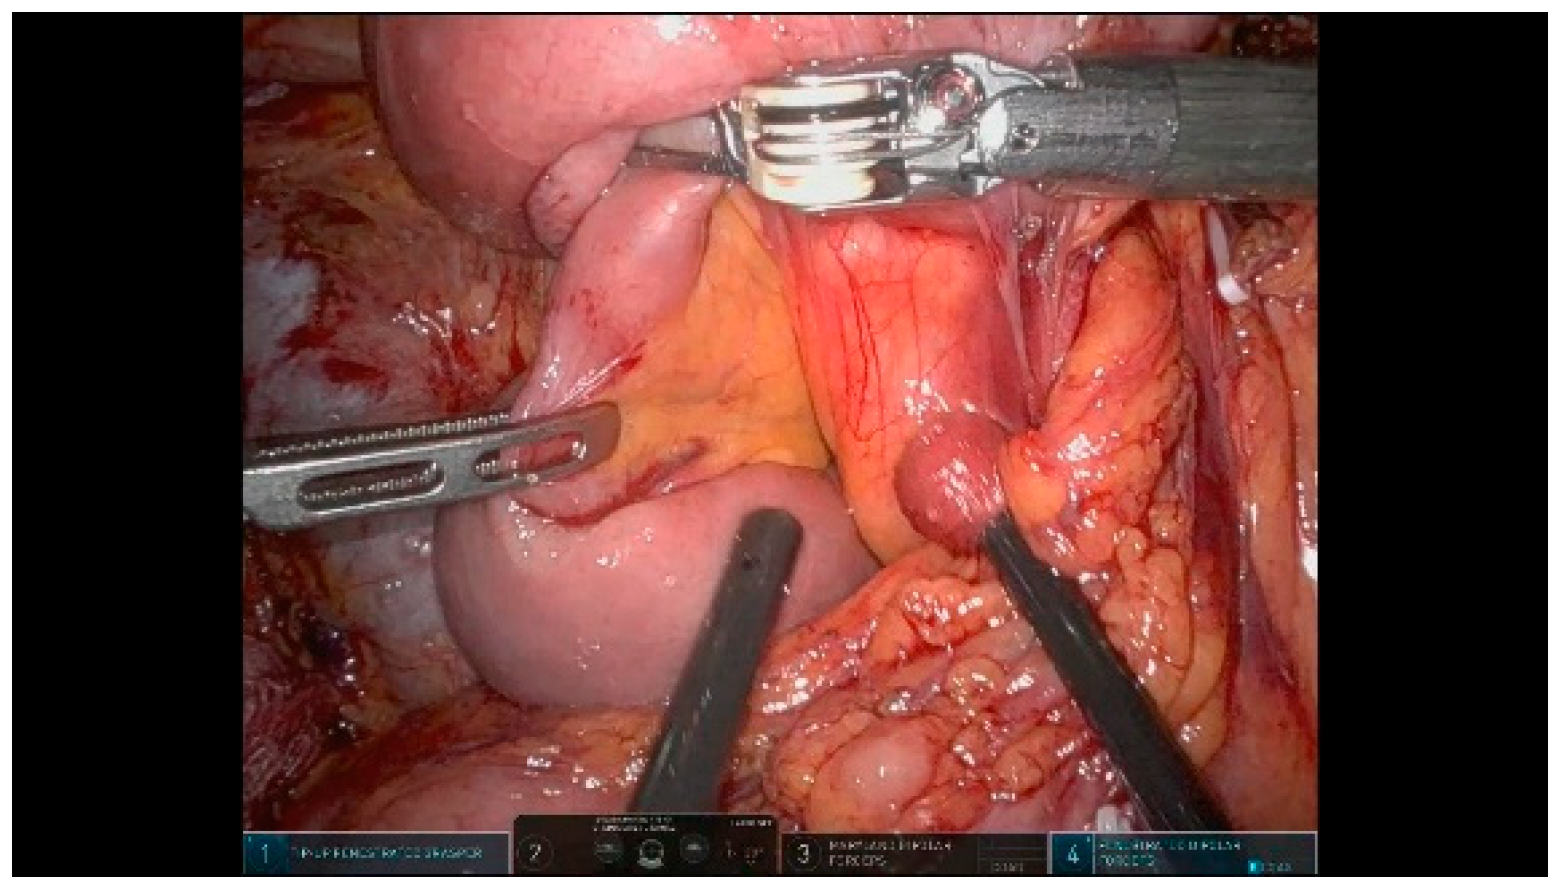

3.1.9. Step 9: Pancreas Transection